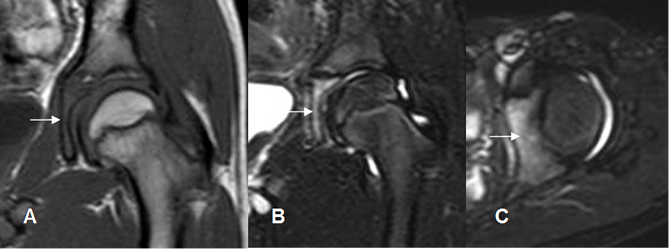

Fig 144 A. Artritis infecciosa.

A: RM coronal en T1, B: RM coronal en STIR y C: RM axial en STIR. Artritis infecciosa con cambios inflamatorios en la parte medial del acetábulo (Flechas), que permite hacer la diferenciación con la sinovitis transitoria.

Fig 144 C. Sinovitis transitoria.

A: RM coronal en STIR y B: RM axial en STIR. Abundante derrame articular y proliferación sinovial. No se encuentran cambios óseos asociados. El cultivo resulto negativo y la clínica cedió con aines luego de 3 días.